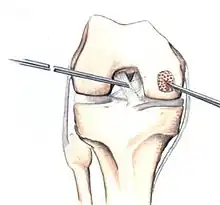

Intact lesions

If non-surgical measures are unsuccessful, drilling may be considered to stimulate healing of the subchondral bone. Arthroscopic drilling may be performed by using an antegrade (from the front) approach from the joint space through the articular cartilage, or by using a retrograde (from behind) approach through the bone outside of the joint to avoid penetration of the articular cartilage. This has proven successful with positive results at one-year follow-up with antegrade drilling in nine out of eleven teenagers with the juvenile form of OCD,[53] and in 18 of 20 skeletally immature people (follow-up of five years) who had failed prior conservative programs.[54]

Hinged lesions

Pins and screws can be used to secure flap (sometimes referred to as hinged) lesions.[55] Bone pegs, metallic pins and screws, and other bioresorbable screws may be used to secure these types of lesions.[56]